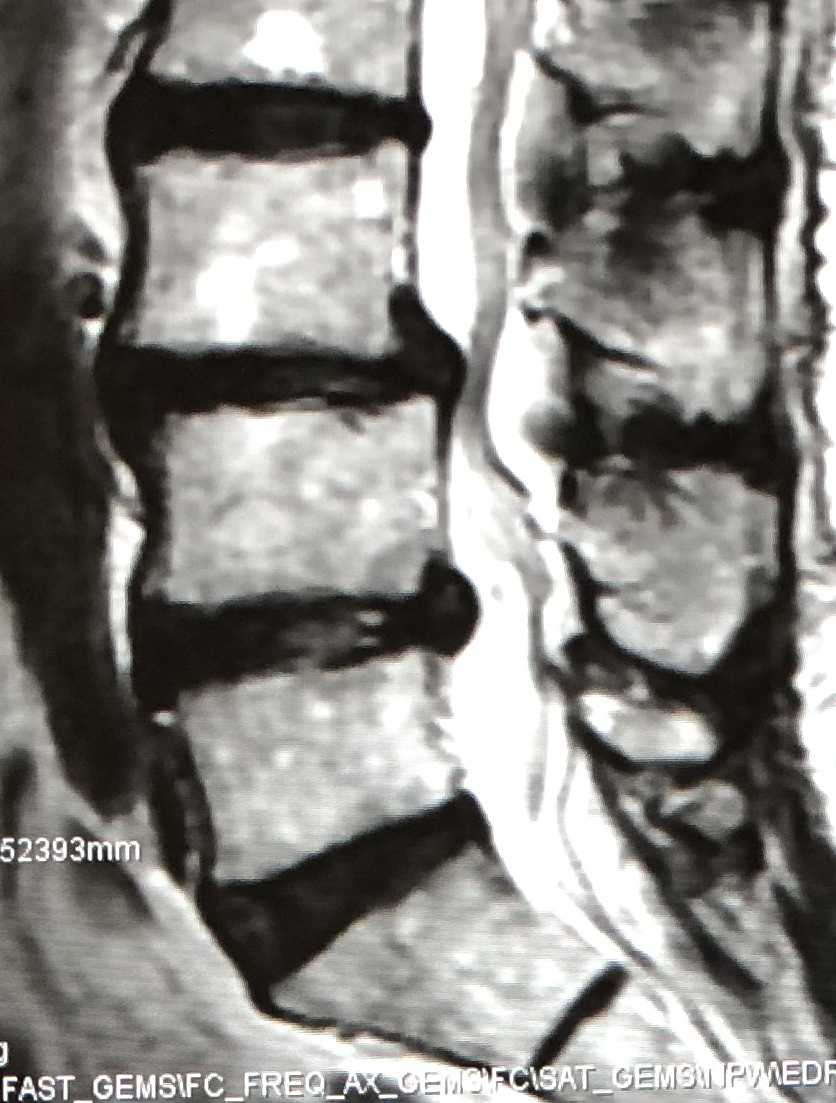

脊椎のすべりにより高度の脊柱管狭窄がある場合に、後方からすべりの矯正や神経の除圧が同時に行える手術です。

| 術前 | 術後 | |

| MRI |

|